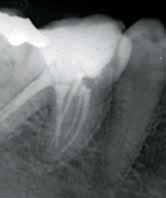

posteriorly on the left palate till the posterior vibrating line. There was no pointing of the lesion. IOPA and occlussal radiographs were taken (Fig1a & b). The IOPA revealed a huge radiolucent lesion with diffuse margins in relation to the periapical region of the upper left lateral which had a root canal filling and a separate smaller radioluscent periapically to the adjacent central incisor also. The occlussal radiograph showeda large radiolucent lesion on the palatal aspect in relation to the upper left lateral. It was decided to retreat the case and the patient was advised of the poor prognosis of the tooth.

Fig 1a: First visit (IOPA) Fig 1b: first visit (occlussal) Fig 2a: Pre obturation 14 months (IOPA) Fig 2b: Pre obturation 14 months (occlussal)